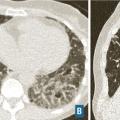

Les symptômes comprennent une dyspnée, une toux, des râles « piaulants » (squeaks) à l’auscultation et parfois des signes généraux semi-retardés : frissons, asthénie, fièvre. Le scanner thoracique met en évidence une atténuation en mosaïque à trois niveaux de densité, des plages de verre dépoli et des nodules flous centrés sur les bronches (fig. 5). Un piégeage aérien est fréquemment retrouvé, et se manifeste par une augmentation du contraste entre zones saines et pathologiques sur les coupes en expiration. Des signes de fibrose sont présents dans les formes fibrosantes. Une lymphocytose > 20-30 % dans le lavage broncho-alvéolaire conforte le diagnostic. L’histologie met en évidence une bronchiolite lymphocytaire, une infiltration interstitielle lymphocytaire, et des granulomes mal définis.